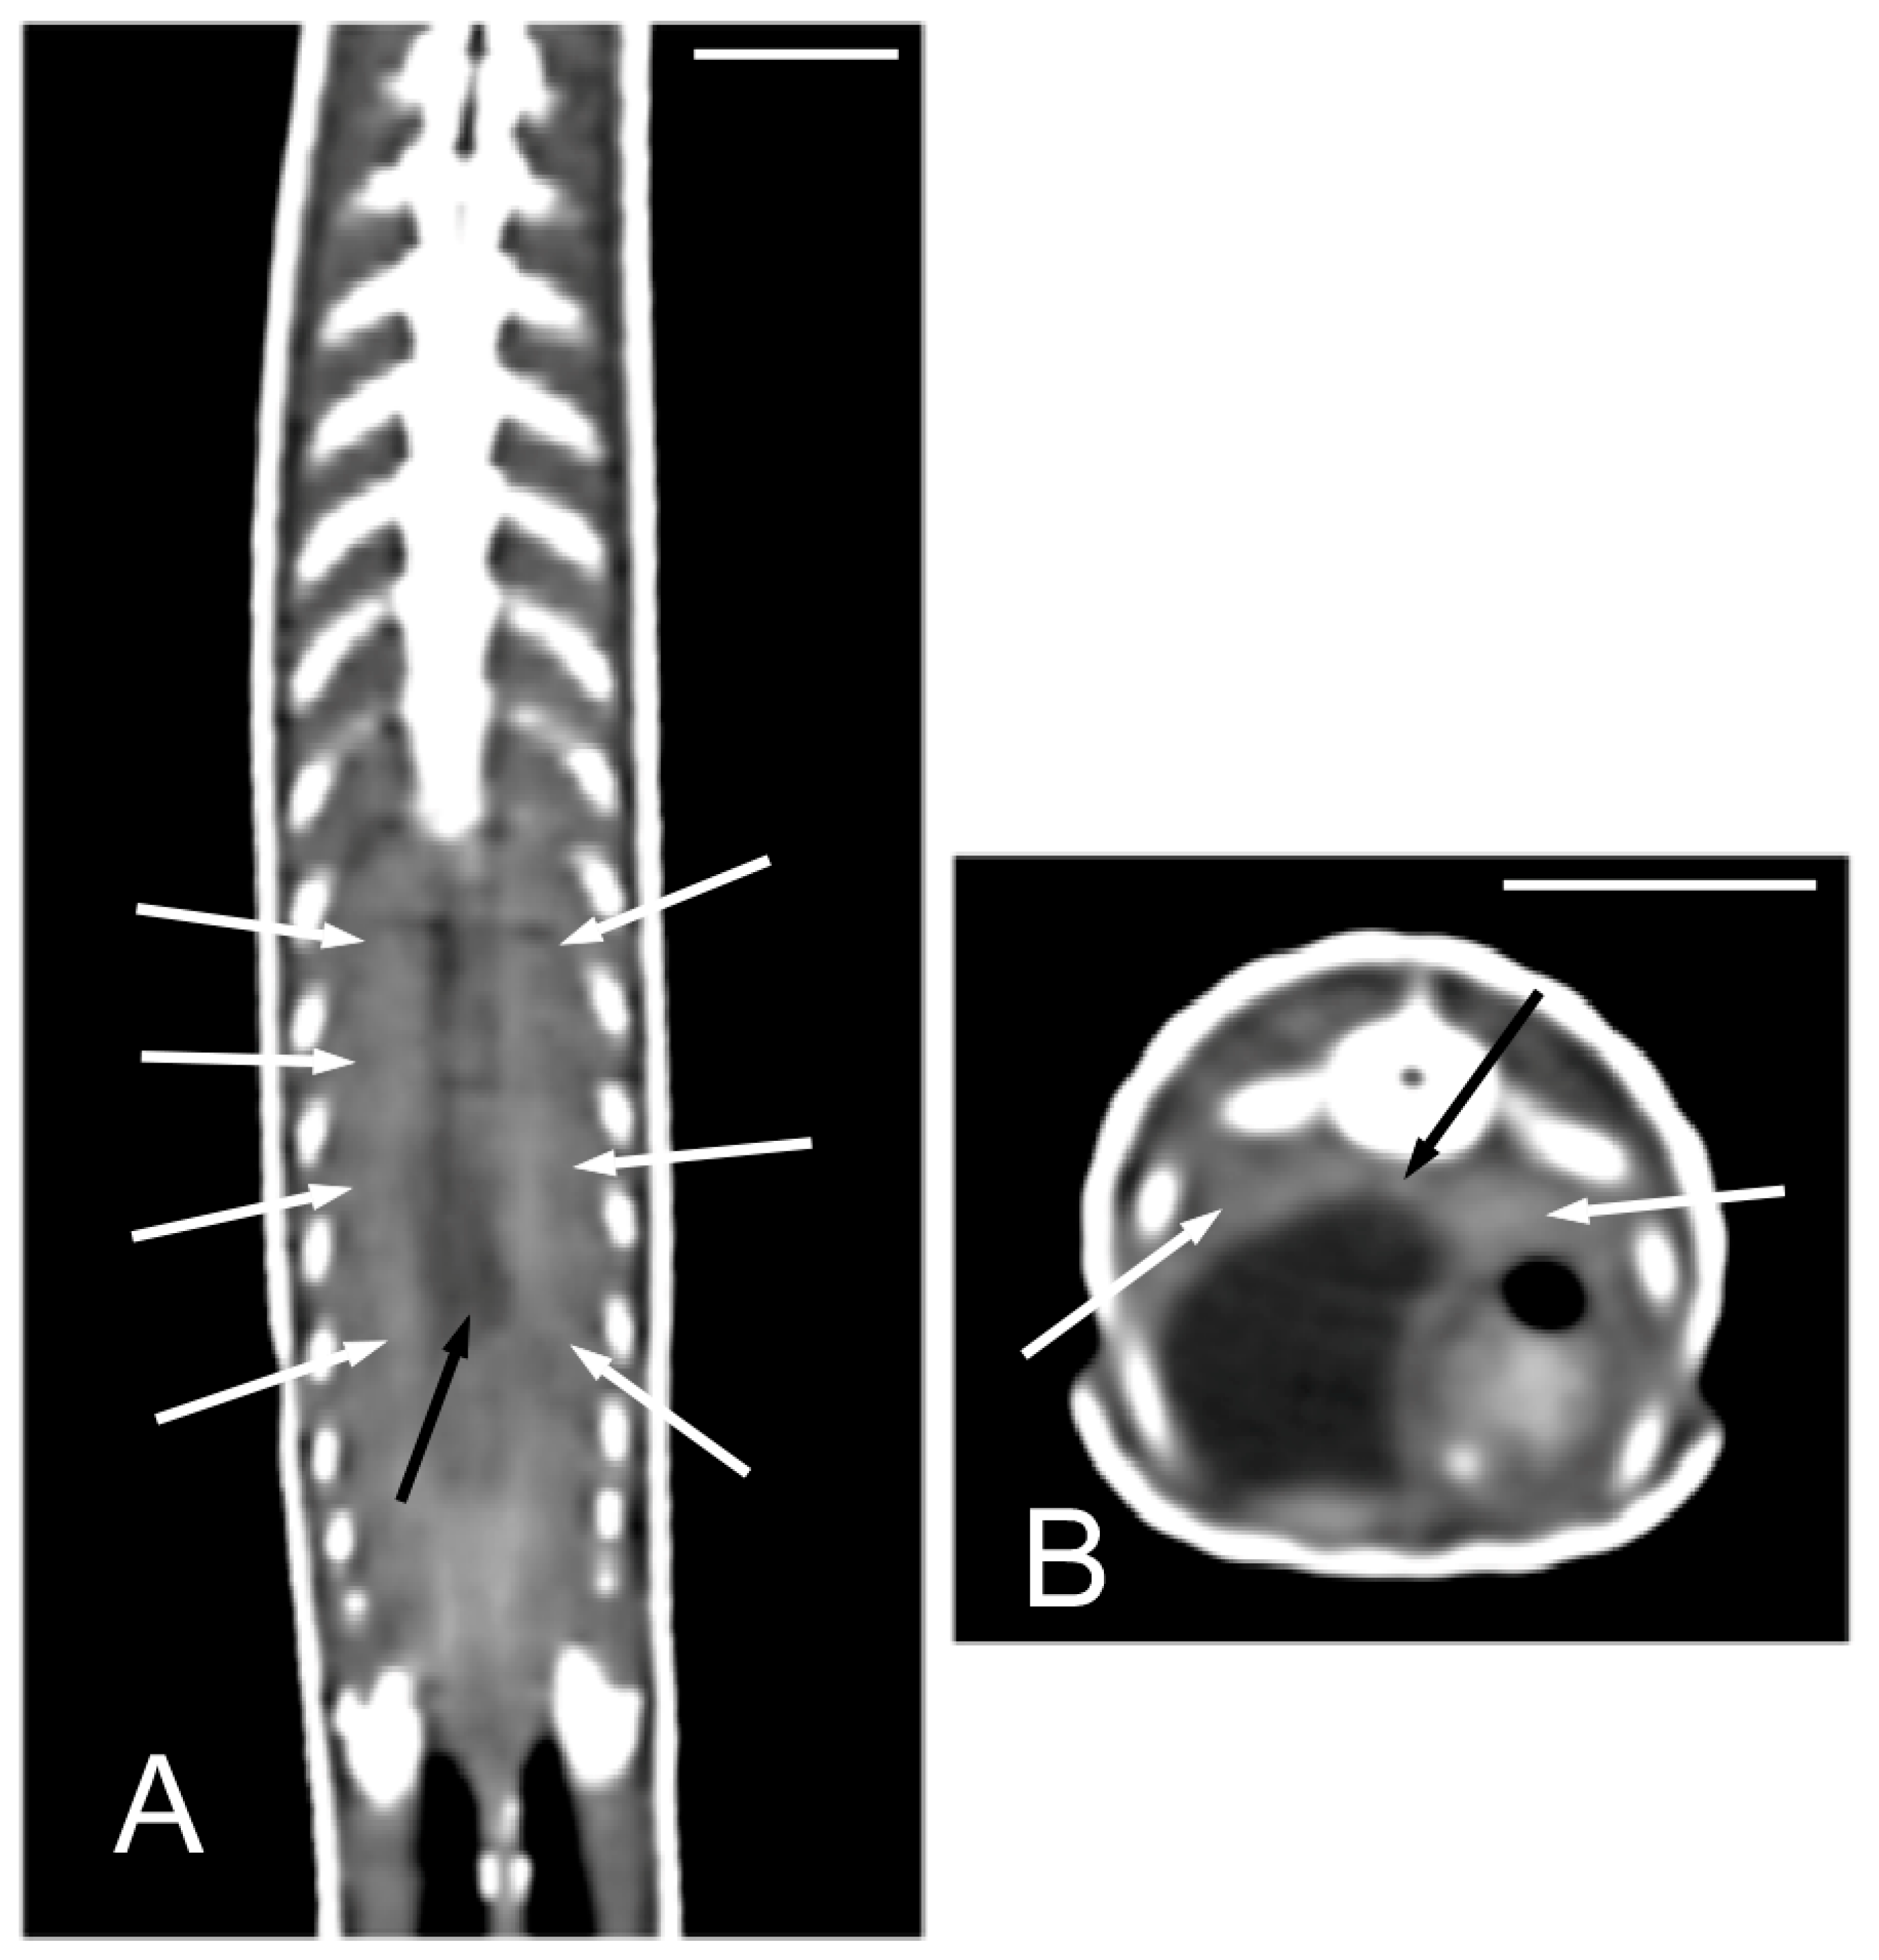

The kidneys and ovaries were identified only in postcontrast CT images. The kidneys appeared as a pair of soft tissue attenuating elongated structures in a ventrolateral position to the spine, in the caudal third of the coelomic cavity. They were best seen in the transverse and dorsal planes. Their margins were not well defined. The aorta was only seen in the midline between them (Figure 13). We could distinguish ovarian follicles only in one individual and they appeared as hypoattenuating rounded to oval structures, bounded by fine slightly hyperattenuating margins (Figure 14). The ureters, urinary bladder, oviducts, testes, and hemipenes were not recognizable in our CT studies.

Figure 13.

The postcontrast CT images of Pseudopus apodus in the dorsal (A) and transverse (B) planes showing both kidneys (white arrows) and the aorta (black arrow) between them in the dorsal part of the coelomic cavity, just ventral to the spine. Bar = 10 mm.

Figure 14.

The postcontrast CT images of Pseudopus apodus in the dorsal (A) and sagittal (B) planes showing ovarian follicles (arrows), just cranial to the kidney. In image A, the aorta (black arrowhead) is identified in the midline. In image B, the white arrowhead points to the right kidney. Bar = 10 mm.